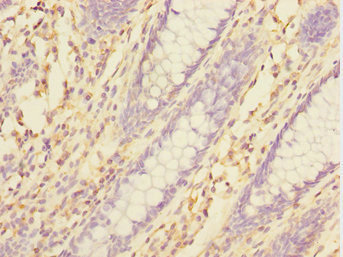

Immunohistochemistry of paraffin-embedded human colon cancer using CSB-PA847679ESR1HU at dilution of 1:100